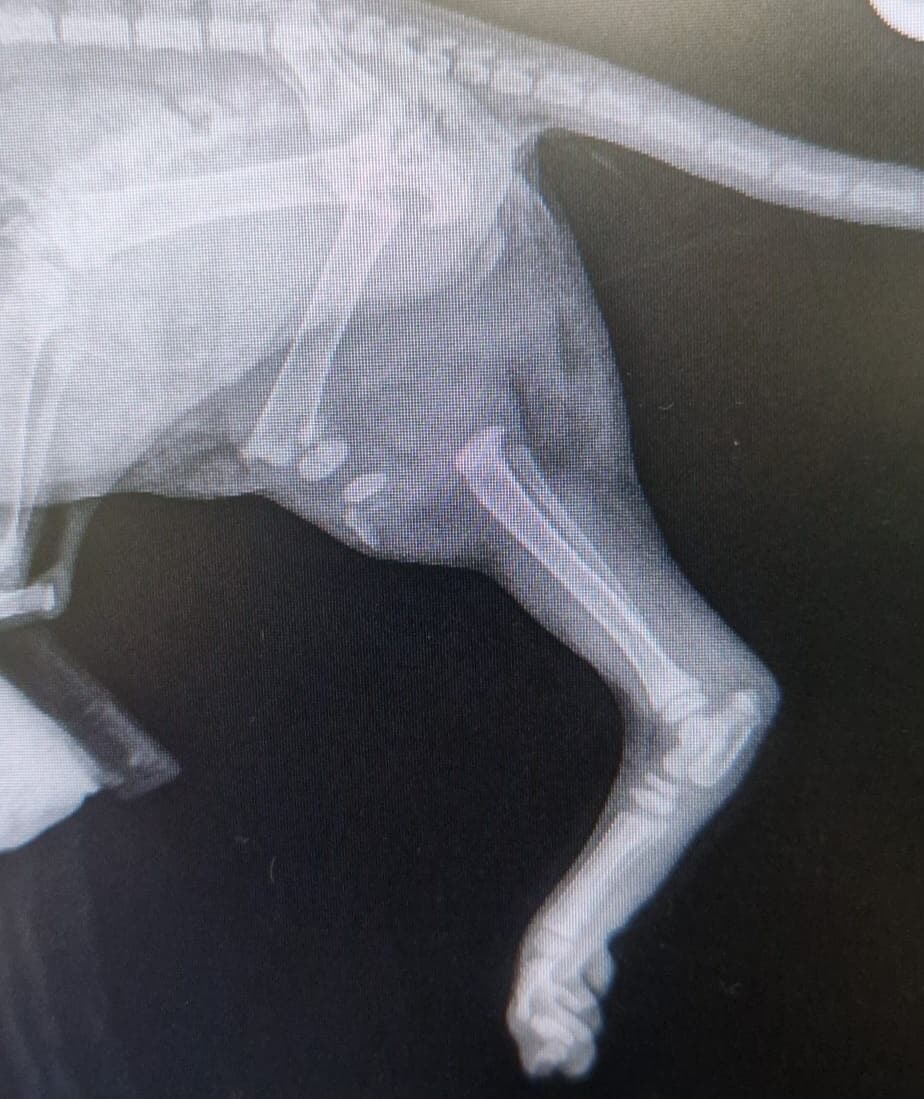

Protect Cats ScotlandThe charity confirmed the youngster’s leg was completely broken, and the vet had no choice but to amputate it.